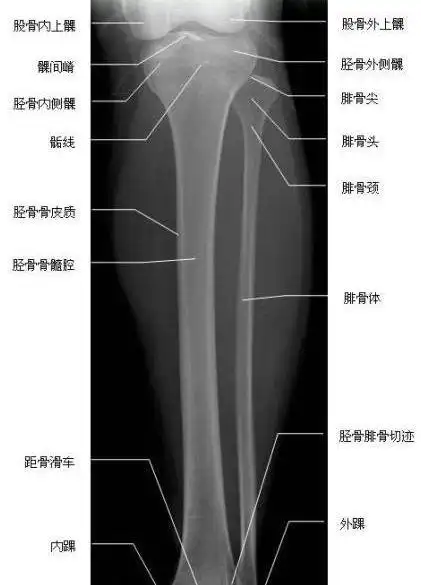

小腿骨(胫腓骨)解剖图谱_医学

下肢x光解剖标记图 - 简书

胫腓骨正位—x线